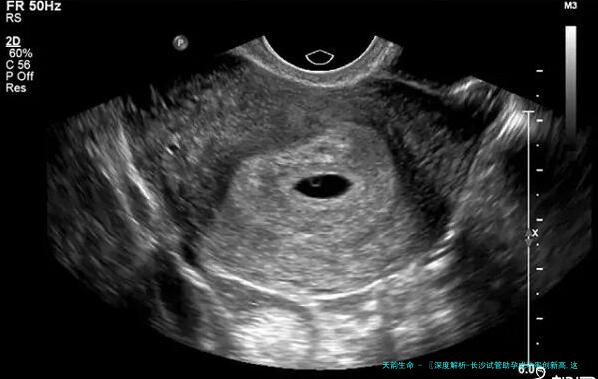

> 从难以开口到坦然面对,越发越多的家庭通过辅助生殖技术迎来了新生命的曙光。

在长沙,试管助孕技术正悄然产生变革性变迁。已往,不少夫妇面对不孕不育的诊断往往感到无助与迷茫,如今,跟着生殖NF的迅猛发展,长沙的试管助孕技术不仅成功率显著提升,更让特定人群收获颇丰。